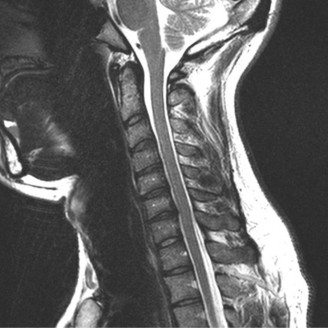

CASE 1 A 63-year-old male sustained a hyperextension injury to his neck while diving into a pool. Upon presentation, he reports decreased sensation in his hands and decreased strength in his arms and wrists, but no lower extremity complaints. On motor examination, he has 5/5 strength in his deltoids and elbow flexors and 4/5 strength in the elbow extensors, wrist extensors, and finger flexors. Lower extremity motor examination is normal. Sensation is decreased to light touch in both hands. Otherwise his sensation is preserved. Images of his cervical spine are shown in Figures 1–1 to 1–3.

Figure 1–1

The correct answer is (B). The clinical scenario describes a patient with central cord syndrome (CCS). CCS continues to be the most common incomplete spinal cord injury accounting for 15.7% to 25% of all spinal cord injuries. The characteristic presentation is an extension moment injury in a previously spondylotic and stenotic spine. Figures 1–1 to 1–3 demonstrate a spondylotic spine with central narrowing and CSF effacement that is worst at the C3–4 level. Bleeding, edema, and/or Wallerian degeneration lead to damage of the lateral corticospinal tract which is the main descending motor tract in the spinal cord. The more central anatomic position of the homunculus to the upper extremities places them at greater risk than those to the lower extremities. As such, injury to the lateral corticospinal tract is characterized by upper more than lower extremity involvement and motor deficits being more pronounced than sensory deficits.